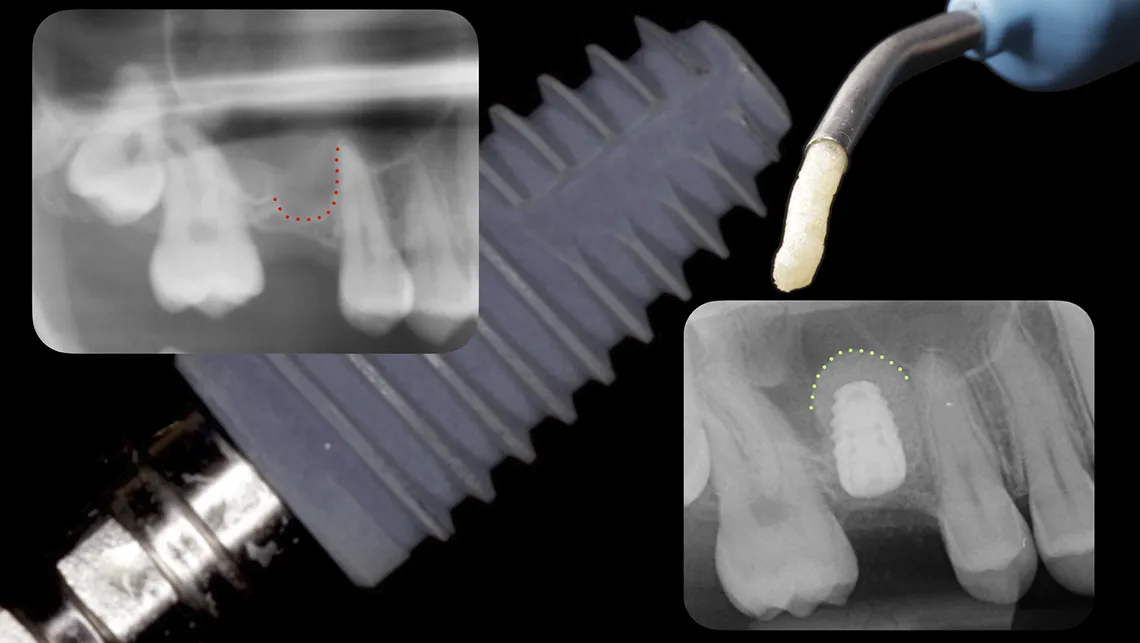

Los estudios disponibles muestran tasas de perforación inferiores al 10% y tasas de éxito cercanas al 97%, incluso en casos con altura ósea residual limitada (figuras 3, 4, 5, 6 y 7).

Fig. 3. Elevación sinusal cerrada. Situación inicial

Fig. 4. Elevación de seno cerrada eficiente. 0,25cc de Biomaterial e implante dental

Fig. 5. Ventana crestal de 4mm de diámetro. Menos es más

Fig. 6. Secuencia de elevación sinusal cerrada. Elevación y compactación del biomaterial

Fig. 7. Elevación sinusal cerrada e implante dental insertado en un solo acto.